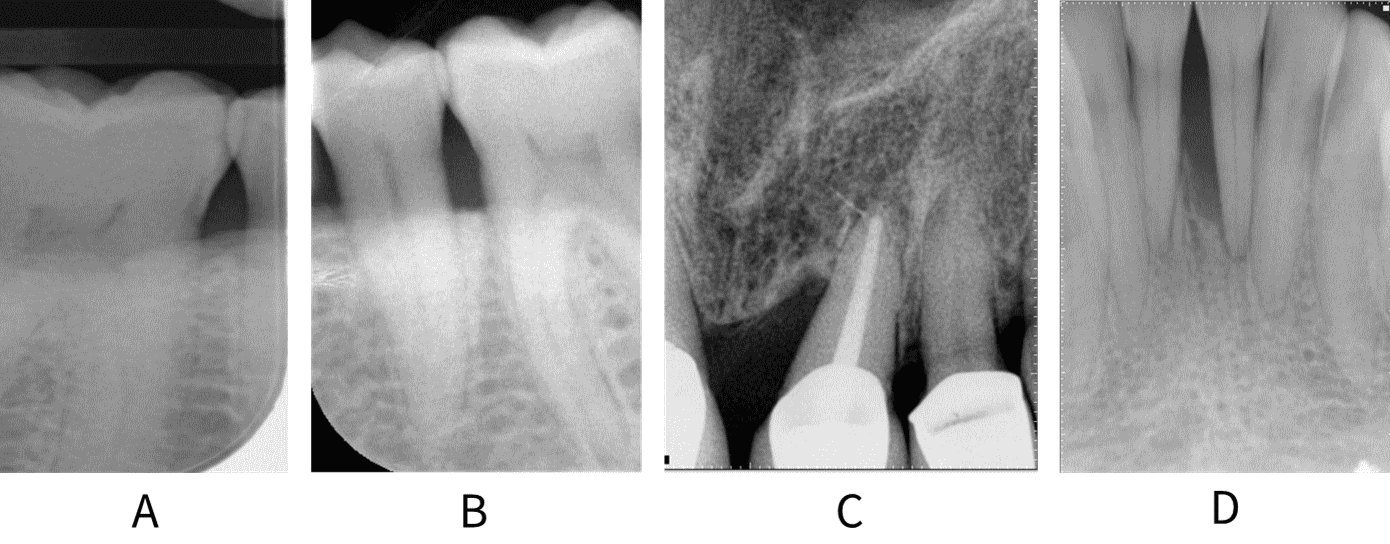

The Stage of periodontitis reflects the historical severity of disease. The Stage of disease is diagnosed using radiographs, ideally those showing the full extent of the root length, and reflects the severity of bone loss at the worst affected site in the mouth (see figure: Stages of periodontitis).

To Stage disease, the worst affected tooth in the mouth is identified radiographically.¥ The amount of bone loss at that worst affected tooth is then calculated as a percentage of the tooth’s total root length. This percentage bone loss is used to determine the Stage (i.e. I – IV) of periodontal disease for that patient overall (see table: Staging periodontal disease). Expressing bone loss as a percentage makes this aspect of diagnosis more objective and allows for easier communication between clinicians and patients.

Radiographs showing A: <15% bone loss between 46 and 45; B: bone loss within the coronal third of the root at 35, 36; C: middle third bone loss on mesial aspect of 21; D: apical third bone loss interdentally at 31, 41.

Diagnosis of early-stage periodontitis may be difficult, and overdiagnosis of disease can be an issue, especially if only bitewing radiographs are available. In these cases, a diagnosis of Stage I periodontitis is assigned if there is >2 mm bone loss but not more than 4 mm. If radiographs are not available, % bone loss can be estimated using CAL from the CEJ; a diagnosis of Stage I periodontitis is assigned if CAL is <2 mm from CEJ.